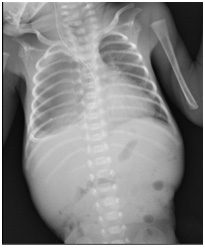

A female newborn weighing 860 gm was delivered by spontaneous vaginal delivery at 26 weeks of gestation. The baby cried immediately after birth and was shifted to a tertiary care hospital NICU for further management, where she received initial supportive care. On Day 17 of life, after insertion of 5 French orogastric tube, the baby’s condition suddenly worsened, and she developed recurrent episodes of apnea requiring mechanical ventilation. A chest radiogram showed the orogastric tube in the right pleural space with a right sided pleural effusion [Table/Fig-1a] . On all previous radiographs, the orogastric tube had been properly positioned. The orogastric tube was removed and a new 5 Fr orogastric tube was reinserted and positioned appropriately, and confirmed both clinically and radiologicaly. The patient was thereafter managed conservatively with no further complications. A radiological dye study was performed 8 days later which showed no leak in esophagus [Table/Fig-1b] , and the baby was gradually weaned off respiratory support. Feeds were reintroduced & gradually increased to full feeds, which were well tolerated, and she was discharged on Day 74 of life.

Chest radiographs showing orogastric tube in right sided pleural space and Pleural effusion